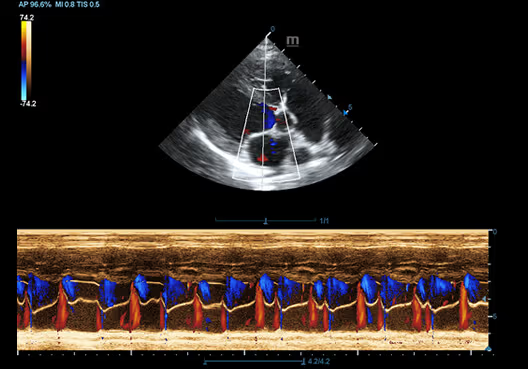

Color M-Mode, Kalp, Köpek

Color M-Mode, Kalp, Köpek